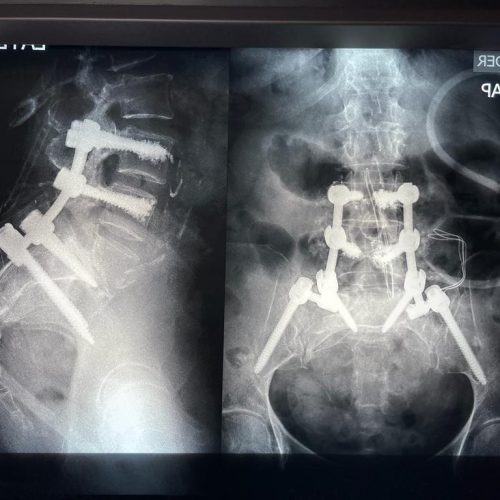

4. Fusión Vertebral (Lumbosacra o Cervical)

¿Qué es?

Cirugía que une dos o más vértebras para estabilizar la columna y aliviar el dolor.

Fusión Vertebral (Cervical o Lumbosacra)

Es un procedimiento quirúrgico que busca estabilizar la columna vertebral uniendo de forma permanente dos o más vértebras. Se utilizan tornillos, barras y, en ocasiones, una caja intersomática con injerto óseo, para que las vértebras se fusionen en una sola unidad sólida.